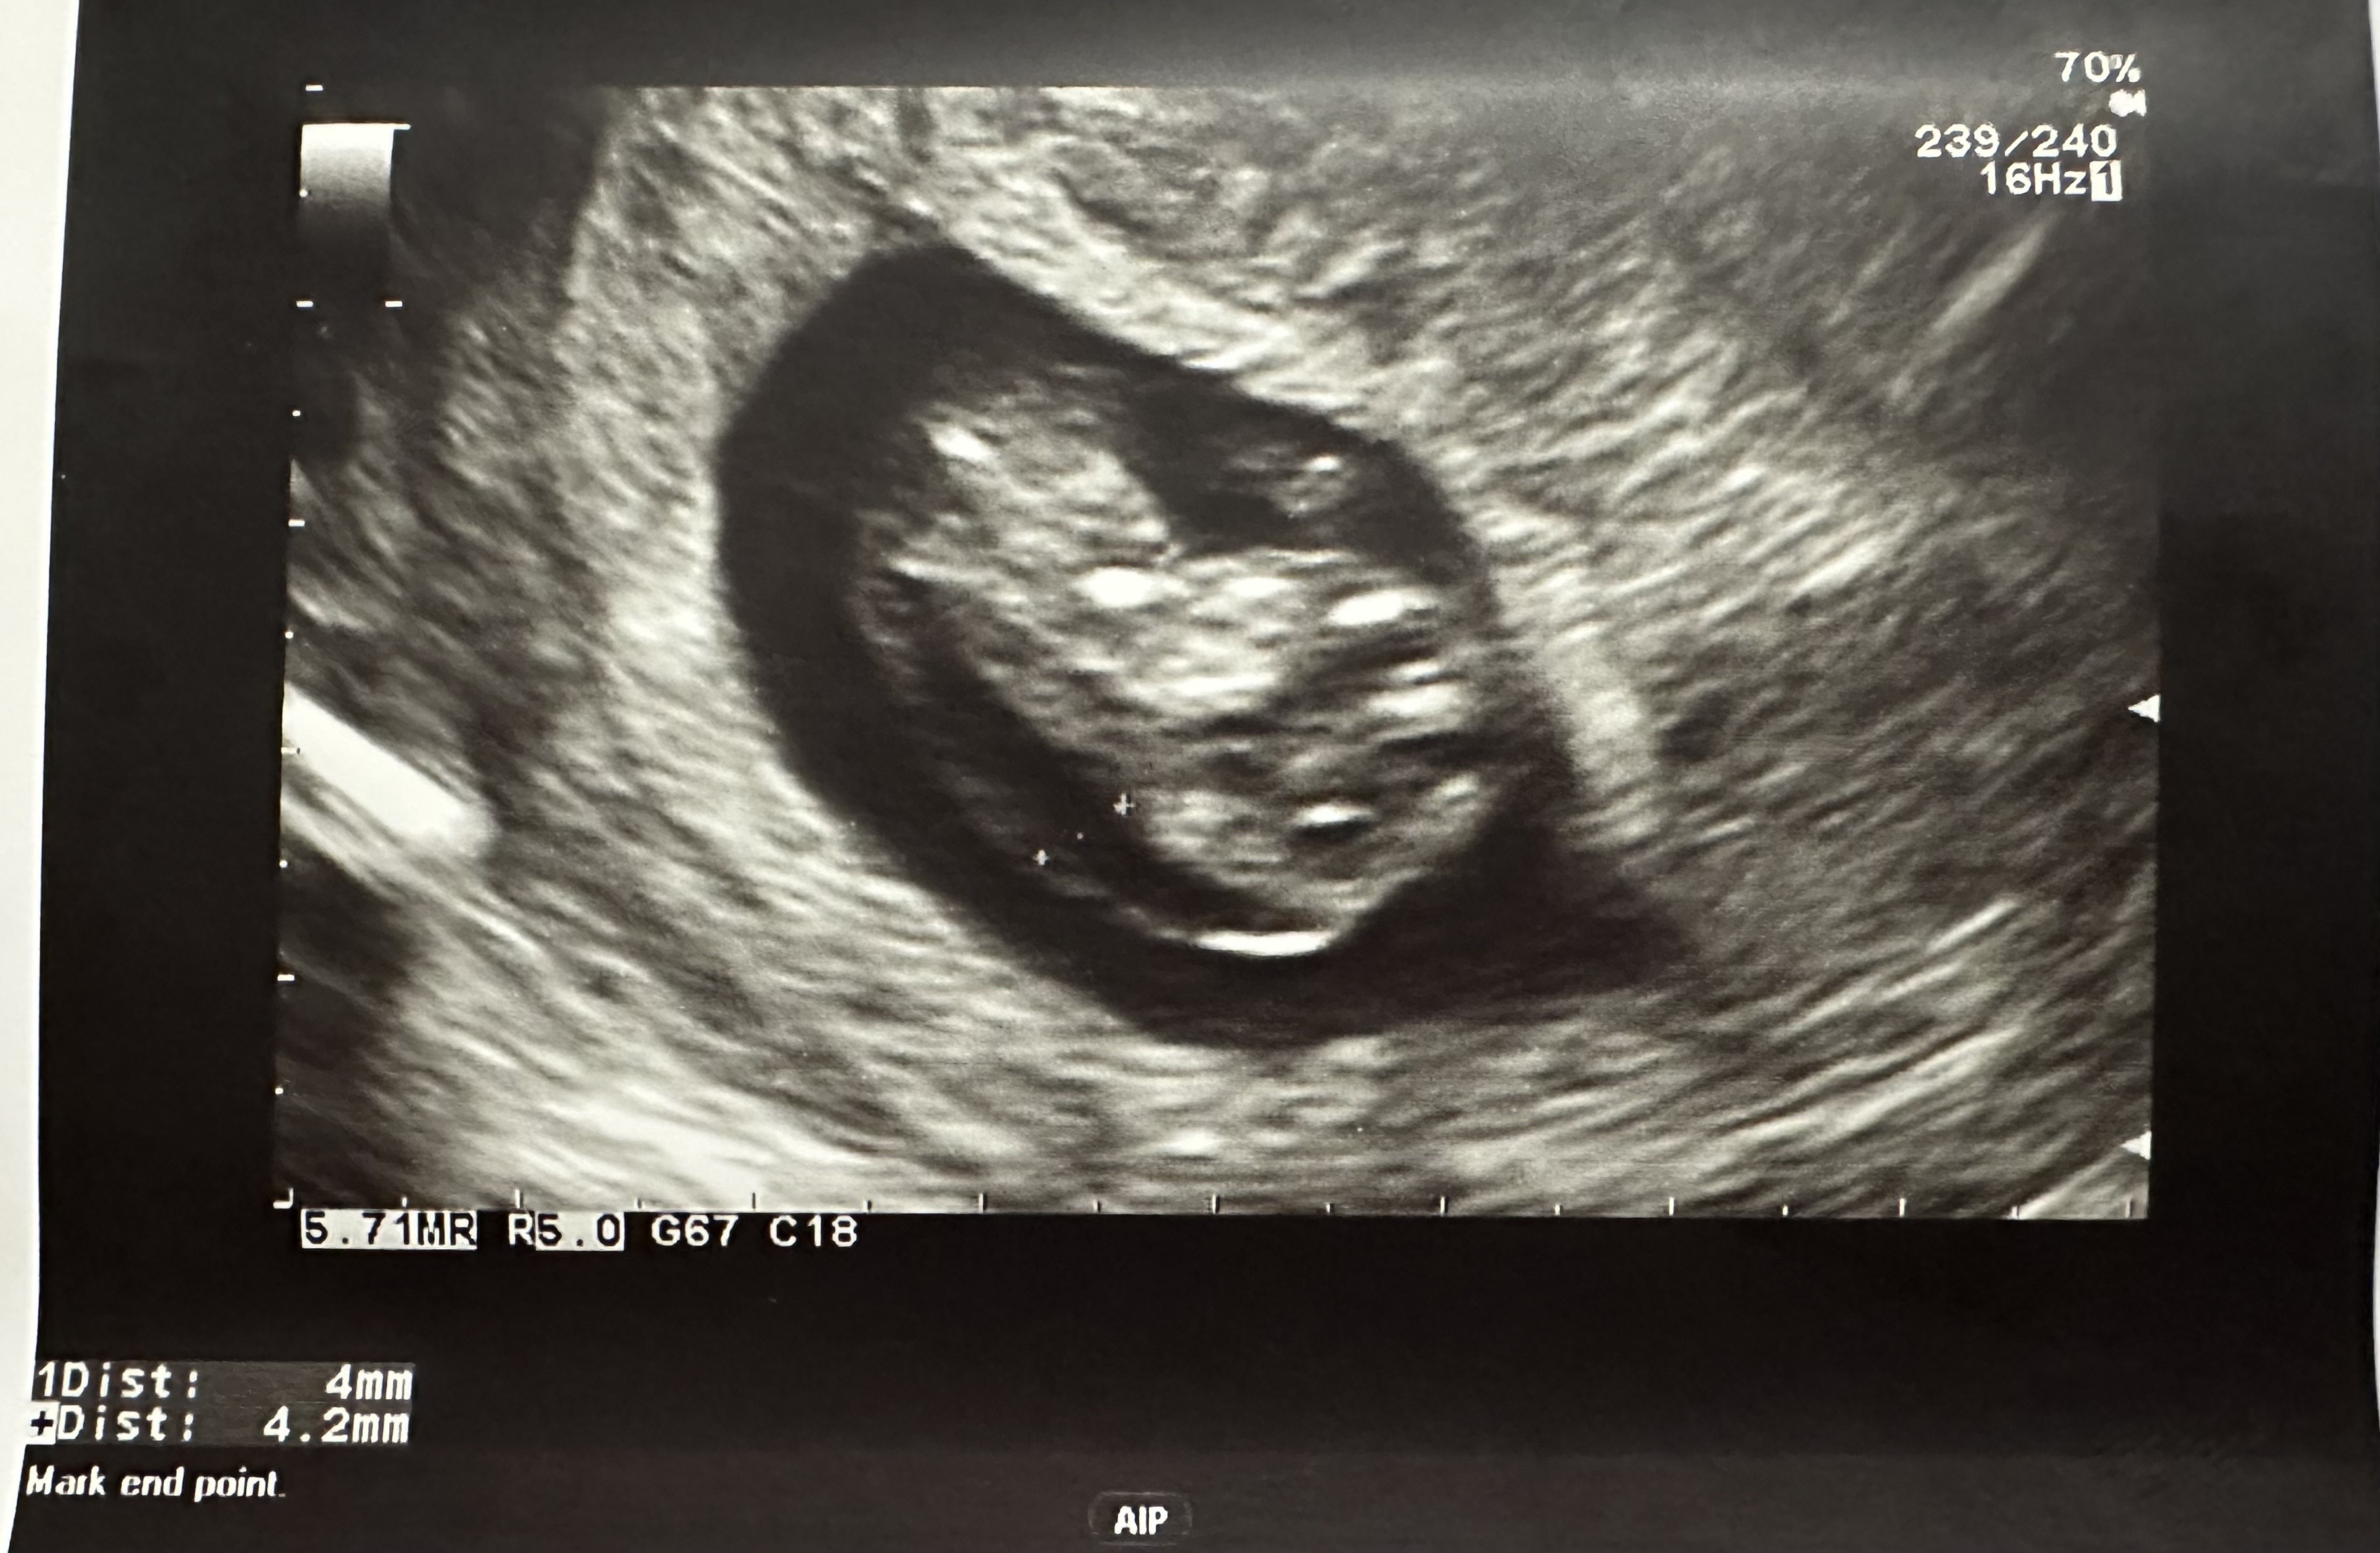

Witam! Mam podobny problem. Byłam na USG w poniedziałek i zdjęcie USG bardzo podobne. Podsyłam w załączniku. W poniedziałek idę na test Nifty, a za tydzień na badania prenatalne na NFZ. Czy możesz powiedzieć co okazało się przyczyna? Mam podobne odczucie - naczytałam się za dużo na temat obrzęku i bardzo się boję. Choć Twoja wiadomość bardzo mnie uskrzydliła! PozdrawiamJa w pierwszej ciąży w 10 tc na badaniu w luxmedzie też usłyszałam, że jest obrzęk - no i lekarka się mnie pytała, czy byłam chora/miałam jakieś infekcje. Akurat byłam zdrowa, więc przez 2 kolejne dni jak się naczytałam o obrzęku płodu to wiadomo, nie było za ciekawieJeszcze wyjeżdżałam na 2 tyg za granicę na urlop i nie miałam jak zrobić USG np za tydzień. Kolejnego dnia byłam na jeszcze jednym USG i ten obrzęk też był widoczny. Na dzień przed wyjazdem zrobiłam Nifty, wyniki przyszły pod koniec urlopu, że jest wszystko ok

poniżej moje USG z tego okresu.

Zobacz załącznik 1603751

Nie znalazłam przyczyny - robiłam badanie na toxo, parwowirus19 i cmv i wyniki były ok. USG z obrzękiem miałam robione chyba koło 9+6 a kolejne dopiero po 3 tygodniach, bo wyjeżdżałam za granicę. I w tym czasie obrzęk zniknął. Na pewno trochę uspokoiły mnie wyniki Nifty, które przyszły w międzyczasie. Trzymam kciuki, aby u Ciebie też wszystko dobrze się skończyłoWitam! Mam podobny problem. Byłam na USG w poniedziałek i zdjęcie USG bardzo podobne. Podsyłam w załączniku. W poniedziałek idę na test Nifty, a za tydzień na badania prenatalne na NFZ. Czy możesz powiedzieć co okazało się przyczyna? Mam podobne odczucie - naczytałam się za dużo na temat obrzęku i bardzo się boję. Choć Twoja wiadomość bardzo mnie uskrzydliła! Pozdrawiam![]()